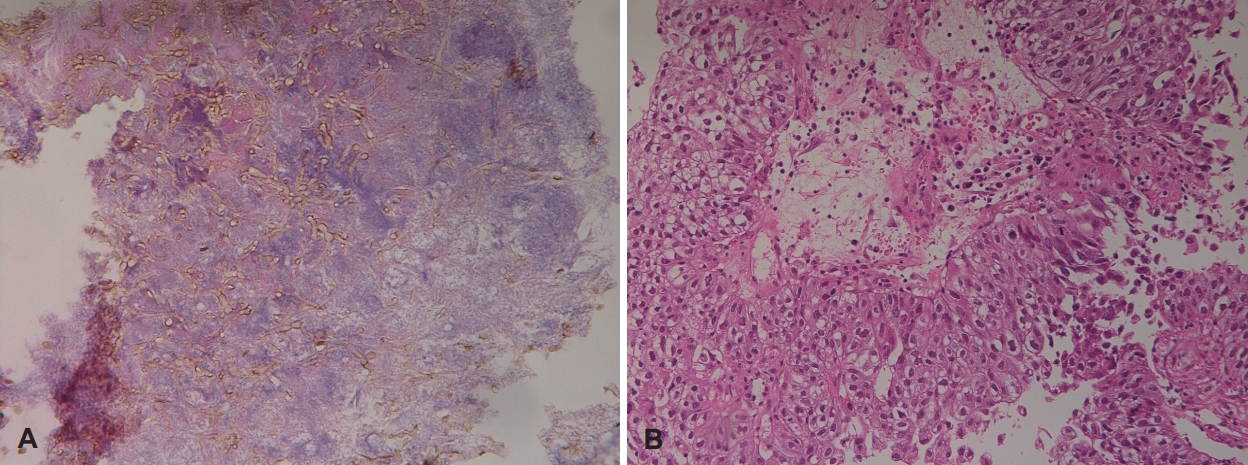

A polyp-like mass of the left nasal cavity was removed, and antrostomy was performed. Mucopurulent clay-like material consistent with a fungal ball was found in the left maxillary sinus. Severe edema was observed in the maxillary mucosa, and biopsy was performed (Fig. 3). Histopathologic examination revealed the diagnosis of a nasal polyp and fungal ball consisting of Aspergillus (Fig. 4A) in the nasal cavity and left maxillary sinus, respectively, as expected. However, unexpectedly, edematous mucosal tissue of the posterior maxillary sinus was confirmed as SCC (Fig. 4B).